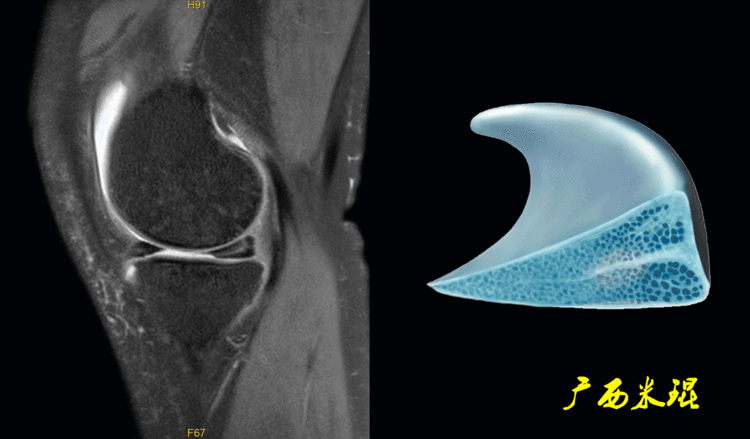

一、半月板损伤MR诊断的思路1、单纯就半月板改变诊断半月板损伤半月板信号(3级信号)及形态的异常是诊断半月板损伤最为直接的征象,当我们在阅片当中发现这些征象,一般情况下都能够确诊半月板损伤,下面这张MR,我们发现外侧半月板后角出现3级信号,所以能够确定其半月板损伤。